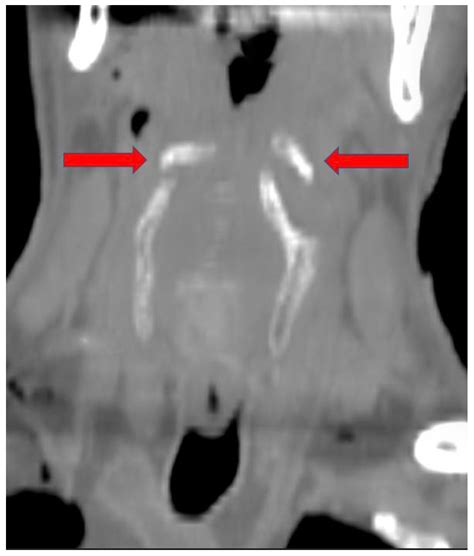

Imaging techniques play a pivotal role in the diagnosis and management of hyoid bone-related conditions. Among these, the Hyoid Bone Coronal CT scan is particularly valuable. This imaging modality provides detailed cross-sectional views of the hyoid bone and surrounding structures, aiding in the accurate diagnosis of various pathologies.

The Hyoid Bone Coronal CT scan involves the following steps:

• Patient Preparation: The patient is positioned supine on the CT table, and the neck is immobilized to minimize movement artifacts.

• Contrast Administration: In some cases, intravenous contrast may be administered to enhance the visualization of soft tissues and blood vessels.

• Image Acquisition: The CT scanner acquires multiple cross-sectional images of the neck in the coronal plane, focusing on the hyoid bone and surrounding structures.

• Image Reconstruction: The acquired images are reconstructed using advanced algorithms to provide high-resolution, detailed views of the hyoid bone.

Interpretation of Hyoid Bone Coronal CT

Interpreting a Hyoid Bone Coronal CT scan requires a thorough understanding of the normal anatomy and potential pathological findings. Key points to consider include:

• Bone Structure: Assess the integrity of the hyoid bone, looking for fractures, erosions, or other abnormalities.

• Soft Tissues: Evaluate the surrounding soft tissues for masses, infections, or other pathological changes.

• Muscles and Ligaments: Examine the muscles and ligaments attached to the hyoid bone for any signs of injury or inflammation.

Radiologists often use a systematic approach to ensure that all relevant structures are carefully evaluated. This includes comparing the findings with previous imaging studies, if available, to detect any interval changes.